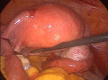

Figure 5

Image coelioscopique après évacuation de la GEU